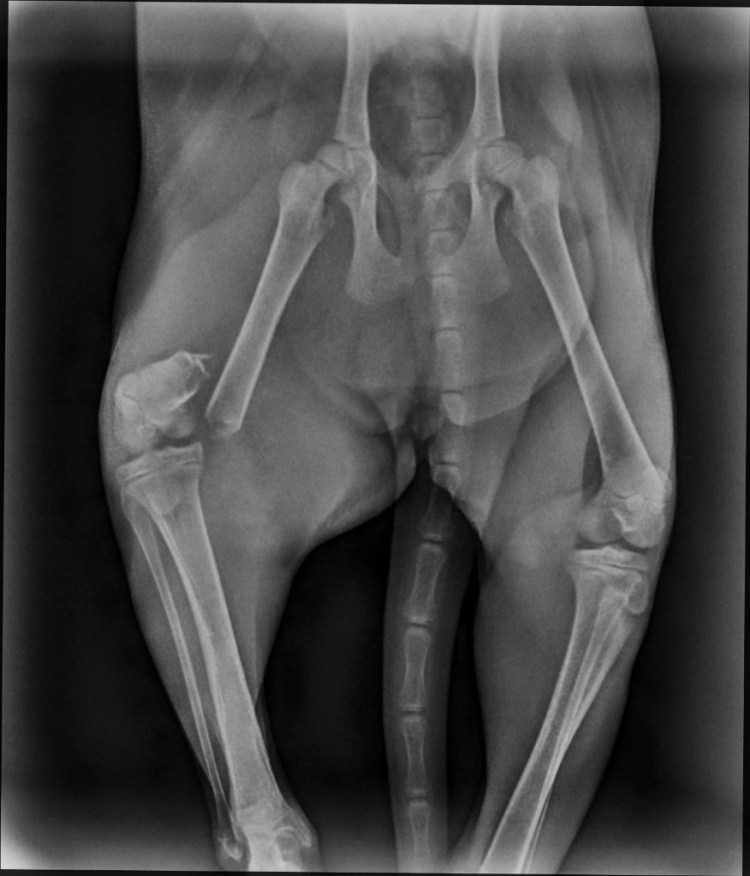

| Krankheiten / Handicaps | Erfolgreiche O.P. nach Oberschenkelbruch |

Beschreibung | Auch Cherry wurde Opfer eines Autounfalls. Natürlich ließ man auch sie einfach liegen und fuhr weiter. Aber sie hatte Glück, der nachfolgende Autofahrer hielt an und brachte sie schnell zum Tierarzt. Die kleine Katzendame hatte einen Bruch am rechten Oberschenkel. Sie wurde operiert und der Bruch wurde mit Stiften fixiert. Inzwischen ist alles gut verheilt und die Stifte auch schon wieder entfernt. Sie hat keine bleibenden Schäden und kann springen und rennen. Nicht mal ein Humpeln ist zurückgeblieben. Nach der O.P. war Cherry sehr unglücklich und traurig im Tierheim. So nahm Silvia auch sie mit nach Hause und sie teilte sich das Gartenhäuschen mit Anita, Aylin, Pantero, Pulgita, Ozzy und Rosa (wir stellen sie separat vor). Cherry ist eine ganz entzückende Katze. Super süß und lieb. Sie schaut gerne aus dem Fenster und hätte zu gerne Freigang. Sie ist neugierig und verspielt, aber nicht zu sehr aktiv. Sie genießt es, mit den anderen Katzenkindern zusammen zu sein und kuschelt gerne mit ihnen im Körbchen. Sie ist devot, sehr friedliebend und hat ein überaus freundliches Wesen. Sie ist eine sehr liebevolle Katze. Cherry vermisst die menschliche Zuneigung. Sie ist ein sehr verschmustes Kätzchen, welches die Kuschel – und Schmuseeinheiten des Menschen braucht. Für Cherry suchen wir ein Zuhause, wo sie für immer bleiben darf und wo man sie lieb hat und man sich mit ihr beschäftigt. Wo sie ihre Schmuse – und Kuscheleinheiten bekommt und wo sie im Bett schlafen darf und ein festes Familienmitglied ist. Das Tierheim ist wieder proppenvoll und so lebt sie derzeit zusammen mit Rosa, Anita und Aylin, Pulgita, Pantero und Ozzy (wir stellen sie alle separat vor. ) bei Silvia auf dem Gelände im Gartenhäuschen. Allerdings ist das nur eine Notlösung. Silvia fehlt einfach die Zeit, um den vier Mädels im Gartenhäuschen ausreichend Schmuseeinheiten zukommen zu lassen. Sie hat 11 Katzen und 2 Hunde bei sich in Pflege. ——————————————————————————- Wir suchen wirklich sehr dringend eine liebe Familie. Auch sie hat in ihrem kleinen Leben bereits genug erlebt. Daher suchen wir für sie eine Endstelle. Eine liebe Familie, wo verschmuste und verspielte Katzenkinder willkommen sind. Bitte bedenken Sie, dass kleine Katzenkinder nicht nebenher laufen. Sie brauchen Zuneigung, Aufmerksamkeit und Betreuung. Man muss ihnen zeigen, dass sie Vertrauen haben und sich sicher fühlen können. Und da darf das Spielen und Schmusen nicht zu kurz kommen. Dafür sollte man ausreichend Zeit aufbringen können. Mit den anderen Katzen versteht sie sich sehr gut und daher kann sie gerne auch zu gleichaltrigen Katzen, die bereits in der Familie leben, hinzu vermittelt werden. Auch mit Hunden kommt sie gut klar. Liebe Kinder sind herzlich willkommen. Sollte noch kein Katzenmädel in Cherrys Alter in der Familie leben, vermitteln wir sie gerne mit einer Freundin aus ihrer jetzigen Gruppe. Z.B. Rosa. Auf keinen Fall wird sie als Einzelkatze oder reine Wohnungskatze vermittelt. Cherry soll Freigang in katzensicherer Umgebung bekommen. Es soll auch ein Haushalt sein, wo eine Katzenklappe vorhanden ist oder noch installiert wird. Cherry wird FIV und Leukose getestet, Tollwut, Schnupfen, Seuche und Leukose geimpft, entwurmt, gechipt und kastriert abgegeben. Seit 29.04. ist Cherry nun auf Pflegeplatz bei Hella in Oststeinbek bei Hamburg. Wer Interesse an Cherry hat, kann sie gerne besuchen kommen. Cherry darf für immer bei ihrer Pflegestelle bleiben 🙂 |